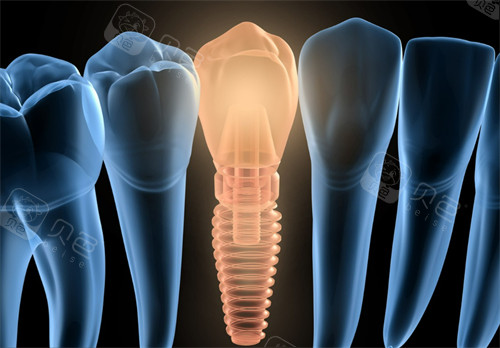

医生水平:患者普遍认可医生可靠度,如种植牙手术“全程痛感低,医生耐心解释方案”。

设备技术:引进高精度口腔CT、智能化牙印机等,提升诊疗效率。